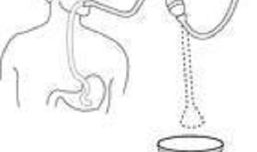

插胃管操作视频,步骤与技巧全解析

你有没有想过,有时候一个简单的操作,背后却隐藏着不少学问和技巧呢?今天,我就要和你聊聊这个话题——插胃管操作视频。是的,你没听错...